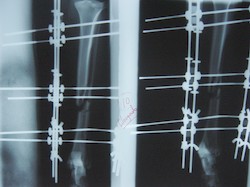

PRÁCTICAS CURSO DE FIJACIÓN EXTERNA PERFECCIONAMIENTO.

Elongacion.